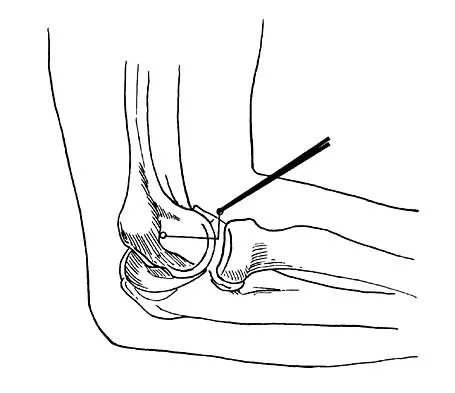

A 16-year-old boy with osteochondritis dissecans of the capitellum has intermittent symptoms of catching and locking. Examination is unremarkable. Radiographs reveal a loose body anteriorly with a diameter of 10 mm. To remove the loose body, elbow arthroscopy is being considered. Which of the following procedures would minimize the risk of neurovascular complication during the procedure?

Explanation